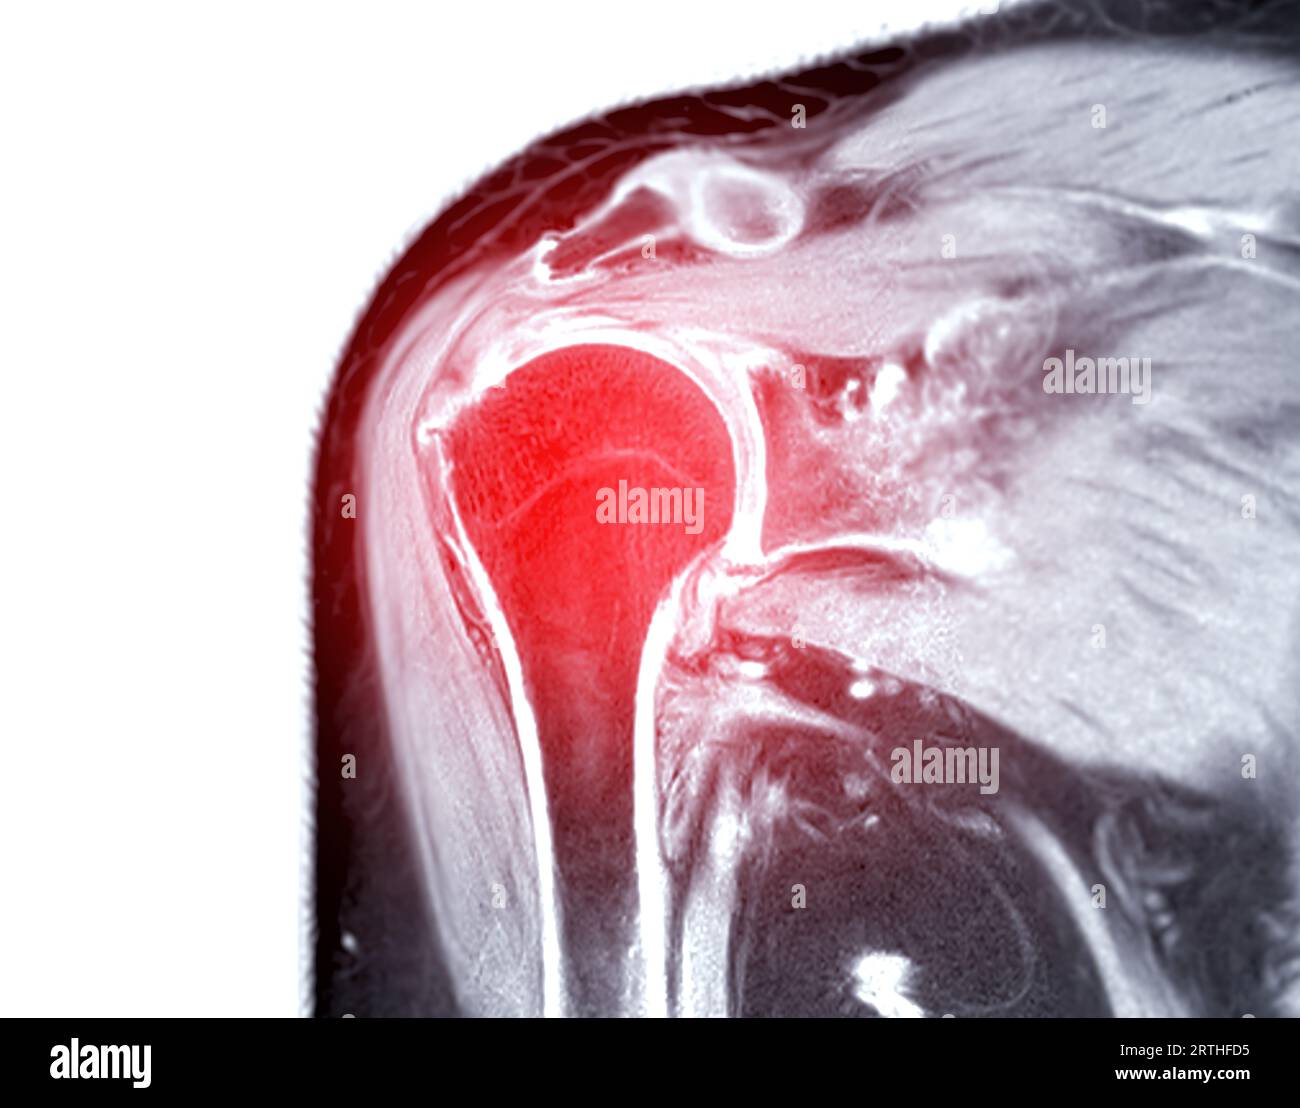

Resonance Imaging or MRI of Shoulder Joint for diagnostic shoulder pain Stock Photo Alamy What Can Mri Of Shoulder Detect A shoulder mri can diagnose tears of the rotator cuff, labrum, and tendons. a shoulder mri is a test that uses a magnetic field to take pictures of your shoulder. magnetic resonance imaging, or mri, uses a magnet to examine the inside of your body, useful for diagnosing shoulder pain and. the evaluation of the shoulder, and. What Can Mri Of Shoulder Detect.

Resonance Imaging or MRI of Shoulder Joint for diagnostic shoulder pain Stock Photo Alamy What Can Mri Of Shoulder Detect in particular, the images include your muscles, ligaments, and cartilage as well as any other components. what can a shoulder mri diagnose? magnetic resonance imaging, or mri, uses a magnet to examine the inside of your body, useful for diagnosing shoulder pain and. A shoulder mri can diagnose tears of the rotator cuff, labrum, and tendons. . What Can Mri Of Shoulder Detect.

Resonance Imaging or MRI of Shoulder Joint for diagnostic shoulder pain Stock Photo Alamy What Can Mri Of Shoulder Detect The mri allows accurate assessment of. the evaluation of the shoulder, and especially its soft tissue structures, is best done with an mri. A shoulder mri can diagnose tears of the rotator cuff, labrum, and tendons. magnetic resonance imaging (mri) of the shoulder is done to: in particular, the images include your muscles, ligaments, and cartilage as. What Can Mri Of Shoulder Detect.